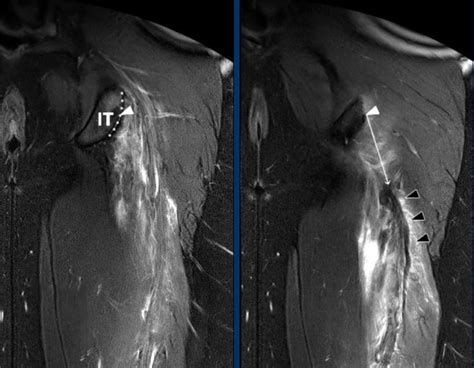

The Radiology Assistant : Hamstring injury

1024×574